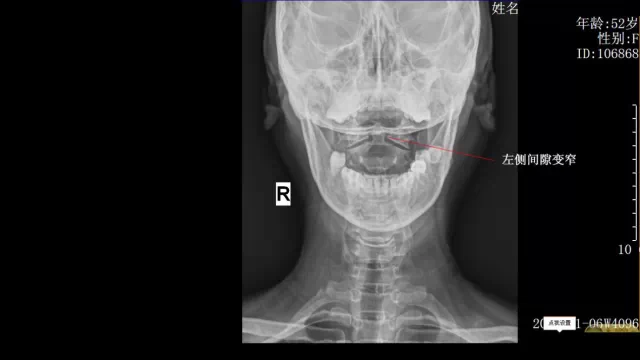

崔阿姨,湖北襄阳人,反复颈背部疼痛、打嗝8年,经多方治疗效果不佳,拍片显示寰枢椎关节失稳,我们对其采用进口的整脊枪结合脊椎的生物力学原理进行整复后,崔阿姨的颈背部疼痛等症状消失,打嗝明显减少。

整脊前